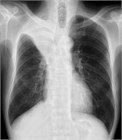

1. 無気肺とは肺組織が虚脱し、肺の含気が低下した状態である。

1. 閉塞性無気肺(腫瘍、粘液栓、異物、気管支結核など)と非閉塞性無気肺(炎症などによる肺実質の虚脱、受動性無気肺、円形無気肺など)に大別される。

1. 胸部X線撮影で無気肺が疑われたら、まずは胸部造影CTで鑑別をすすめ、必要に応じ喀痰培養、喀痰細胞診、気管支鏡などを行う。